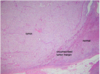

Pheochromocytoma

Pheochromocytoma

Pheochromocytoma